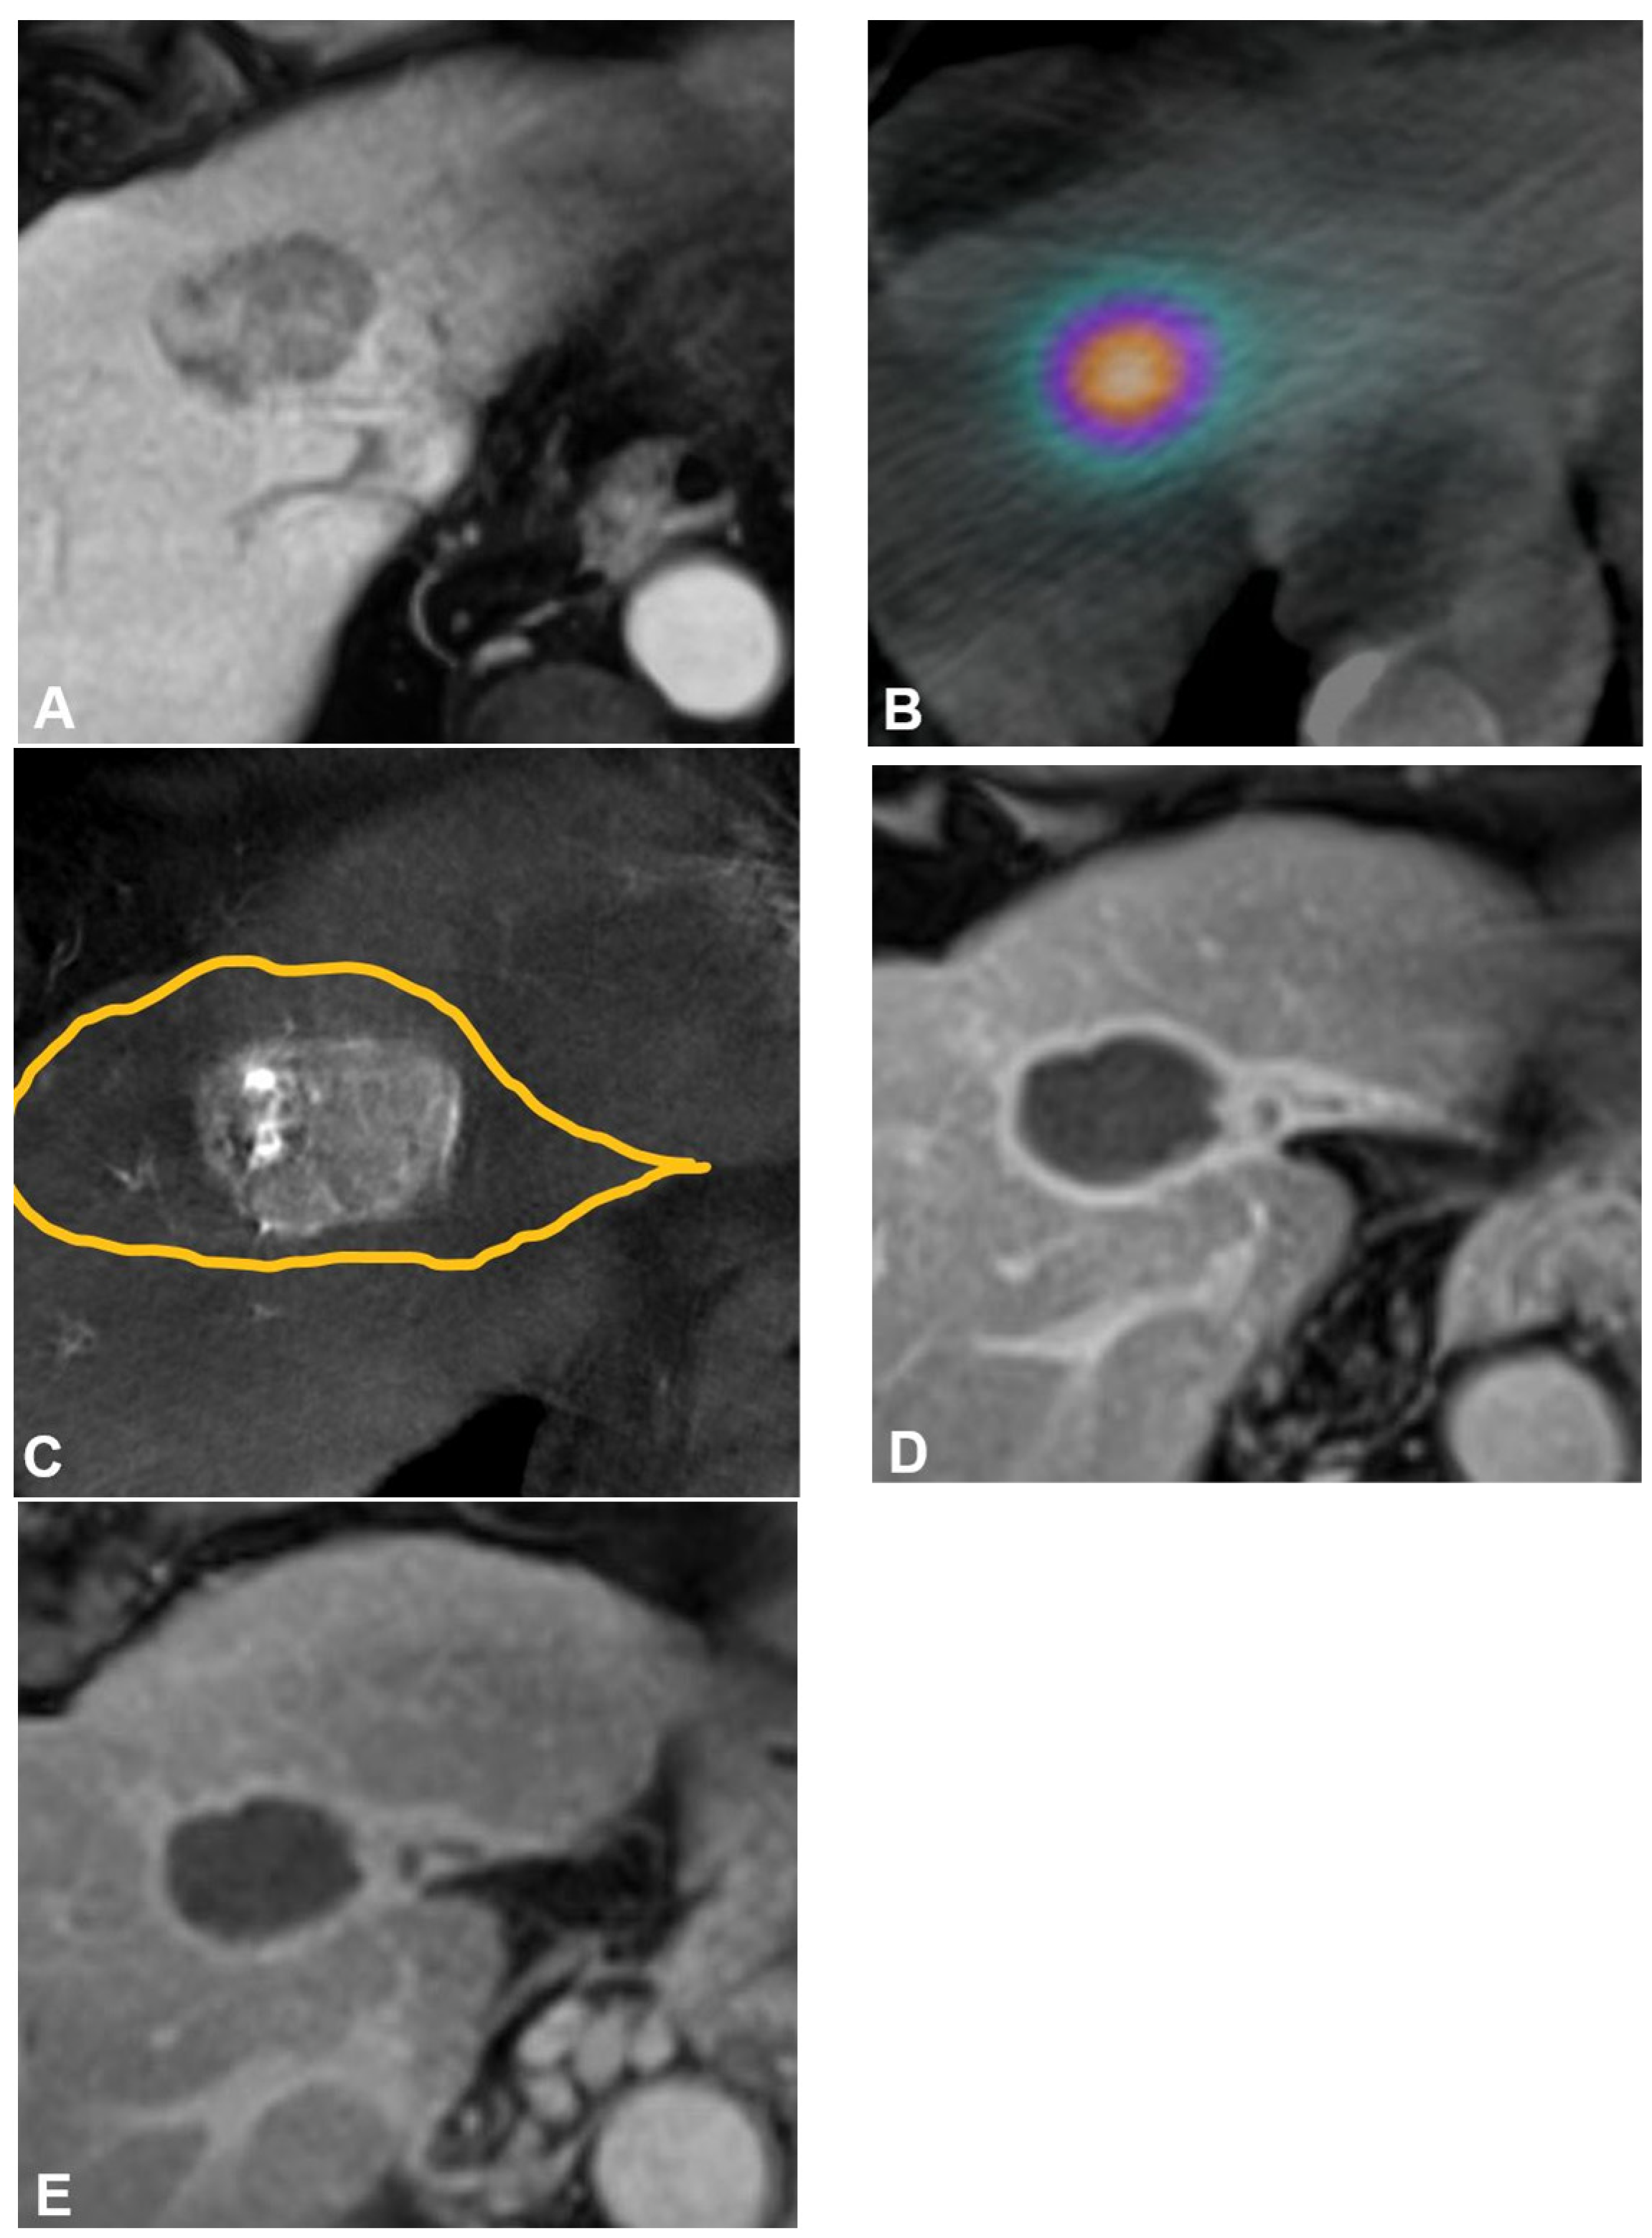

Treatment commonly occurs one to four weeks after mapping and consists of selective transarterial infusion of Y90-containing microspheres within target vessels followed by Bremsstrahlung SPECT/CT or Y90 PET/CT to confirm particle deposition (Figure 1). To enhance dose delivery to the tumor and reduce other nontarget uptake, flow diversion prior to radiation segmentectomy using coils, balloon occlusion, gel foam, and plugs can be implemented when indicated [22,23,24]. Same-day mapping and treatment are now being performed more often to expedite oncologic care [25,26,27]. Recent studies suggest that pretreatment 99mTc-MAA be omitted in patients with early-stage HCC due to the low LSF and risk of radiation pneumonitis in patients with these baseline tumor characteristics and absence of a transjugular intrahepatic portosystemic shunt [28].

Figure 1.

Radiation segmentectomy as sole therapy for hepatocellular carcinoma in a patient with a history of hepatitis C virus, stage 4 fibrosis, and ALBI 1 and Child-Pugh A5 liver function. (A) Pretreatment axial contrast-enhanced MRI demonstrates a 4.3 cm tumor in hepatic segment Iva. (B) Cone-beam CT performed at the time of mapping angiography demonstrates the arterially enhancing target tumor is fed by a segment IVa hepatic artery. The yellow line delineates the estimated treatment angiosome. (C) Posttreatment axial SPECT/CT confirms activity within the targeted angiosome and absent extrahepatic deposition. The estimated radiation dose was 870 Gy MIRD. Follow-up axial contrast-enhanced MRI obtained (D) 12 months and (E) 52 months after therapy demonstrate no evidence of residual or recurrent disease, and contraction of the treated angiosome.